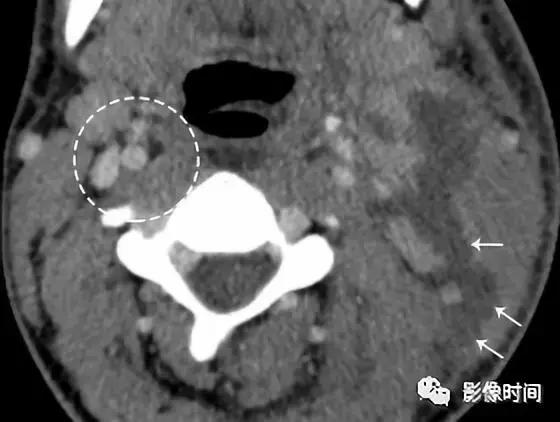

增强 CT 显示左侧颈深淋巴结环形强化 (白色箭头),伴液化性坏死 (星形),左颈内动脉 (IC) 受压后内移位。3 天后显示化脓性淋巴结破裂 (箭头),注意正常的右侧颈动脉间隙保留的脂肪间隙 (圆圈)。化脓性淋巴结破裂,液体渗入到颈动脉间隙 (箭头)。